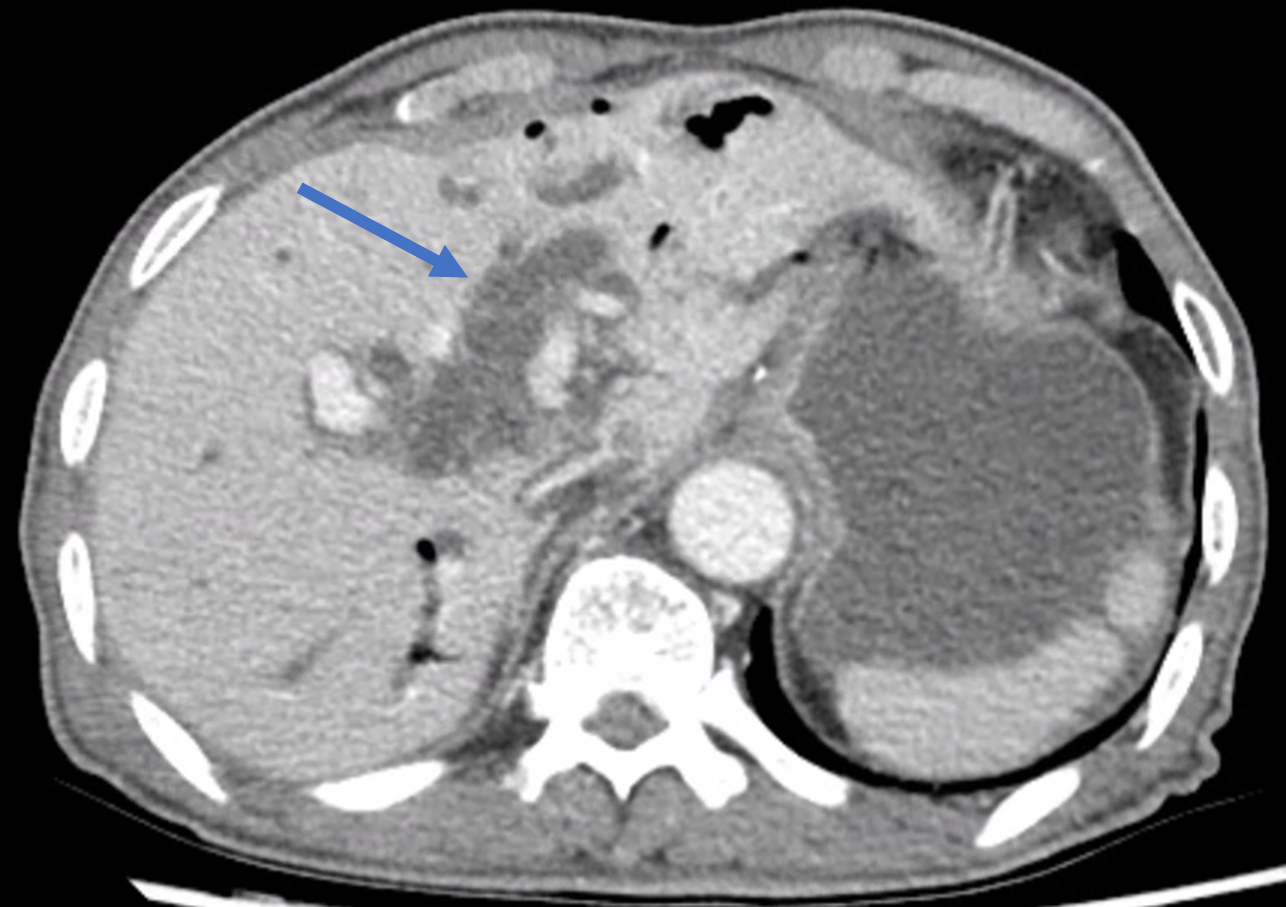

먼저 CT를 촬영해야 하고요.

CT 촬영에서 이 환자에게 이 시술이 정말 필요한 상황인지, 시술 자체에 어려움이나 합병증을 유발할 만한 다른 요인은 없는 지 확인합니다.

위에 제가 올린 CT 처럼 간내담관이 아주 늘어난 경우에는 초음파로도 담관이 잘 보입니다.